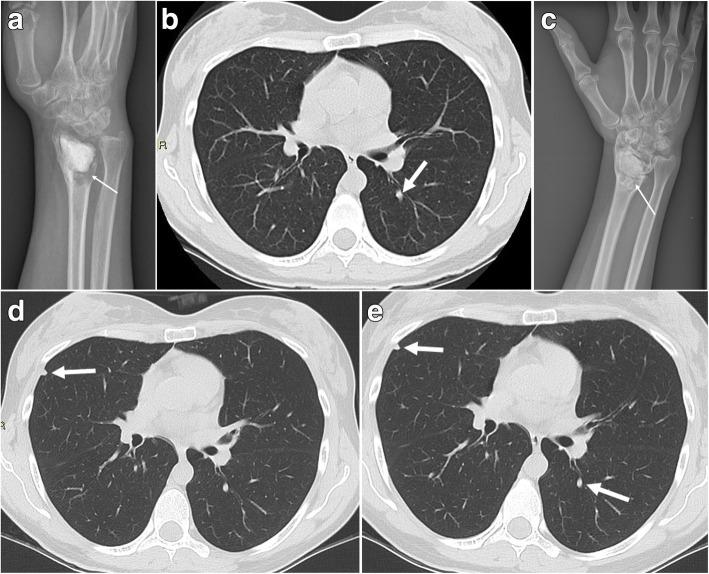

The outcomes of patients with lung metastases from giant cell tumor of bone (GCTB) vary from spontaneous regression to uncontrolled growth. To investigate whether observation is an appropriate first-line management approach for patients with lung metastases from GCTB, we evaluated the outcomes of patients who were initially managed by observation.

We retrospectively reviewed the data of 22 patients with lung metastases from histologically confirmed GCTB who received observation as a first-line treatment approach. The median follow-up period was 116 months.

Disease progression occurred in 12 patients (54.5%). The median interval between the discovery of lung metastases and progression was 8 months. Eight patients underwent metastasectomy following initial observation. The median interval between the discovery of lung metastases and treatment by metastasectomy was 13.5 months. None of the patients experienced spontaneous regression. Of the 22 patients, 36.4% needed a metastasectomy, and 9.1% required denosumab treatment during the course of the follow-up period. Disease progression occurred in 45.5% of the 11 patients with lung nodules ≤ 5 mm, while all five of the patients with lung nodules > 5 mm experienced disease progression. Progression-free survival was significantly worse in the group with lung nodules > 5 mm compared to the group with lung nodules ≤ 5 mm (p = 0.022).

Observation is a safe first-line method of managing patients with lung metastases from GCTB. According to radiological imaging, approximately half of the patients progressed, and approximately half required a metastasectomy or denosumab treatment. However, patients with lung nodules > 5 mm should receive careful observation because of the high rate of disease progression in this group.

患有骨巨细胞瘤(GCTB)肺转移的患者的结局从自发消退到不受控制的生长不等。为了研究观察是否是 GCTB 肺转移患者的一线治疗方法,我们评估了初始接受观察治疗的患者的结局。

我们回顾性分析了 22 例经组织学证实的 GCTB 肺转移患者的资料,这些患者接受了观察作为一线治疗方法。中位随访时间为 116 个月。

12 例患者(54.5%)发生疾病进展。从发现肺转移到进展的中位间隔时间为 8 个月。8 例患者在初始观察后接受了转移灶切除术。从发现肺转移到接受转移灶切除术的中位间隔时间为 13.5 个月。没有患者出现自发性消退。在 22 例患者中,有 36.4%需要进行转移灶切除术,9.1%需要在随访期间使用地舒单抗治疗。肺结节≤5mm 的 11 例患者中有 45.5%发生疾病进展,而所有 5 例肺结节>5mm 的患者均发生疾病进展。肺结节>5mm 的患者无进展生存率明显差于肺结节≤5mm 的患者(p=0.022)。

观察是 GCTB 肺转移患者安全的一线治疗方法。根据影像学检查,约有一半的患者进展,约有一半的患者需要进行转移灶切除术或地舒单抗治疗。然而,由于这组患者疾病进展率较高,肺结节>5mm 的患者应接受密切观察。